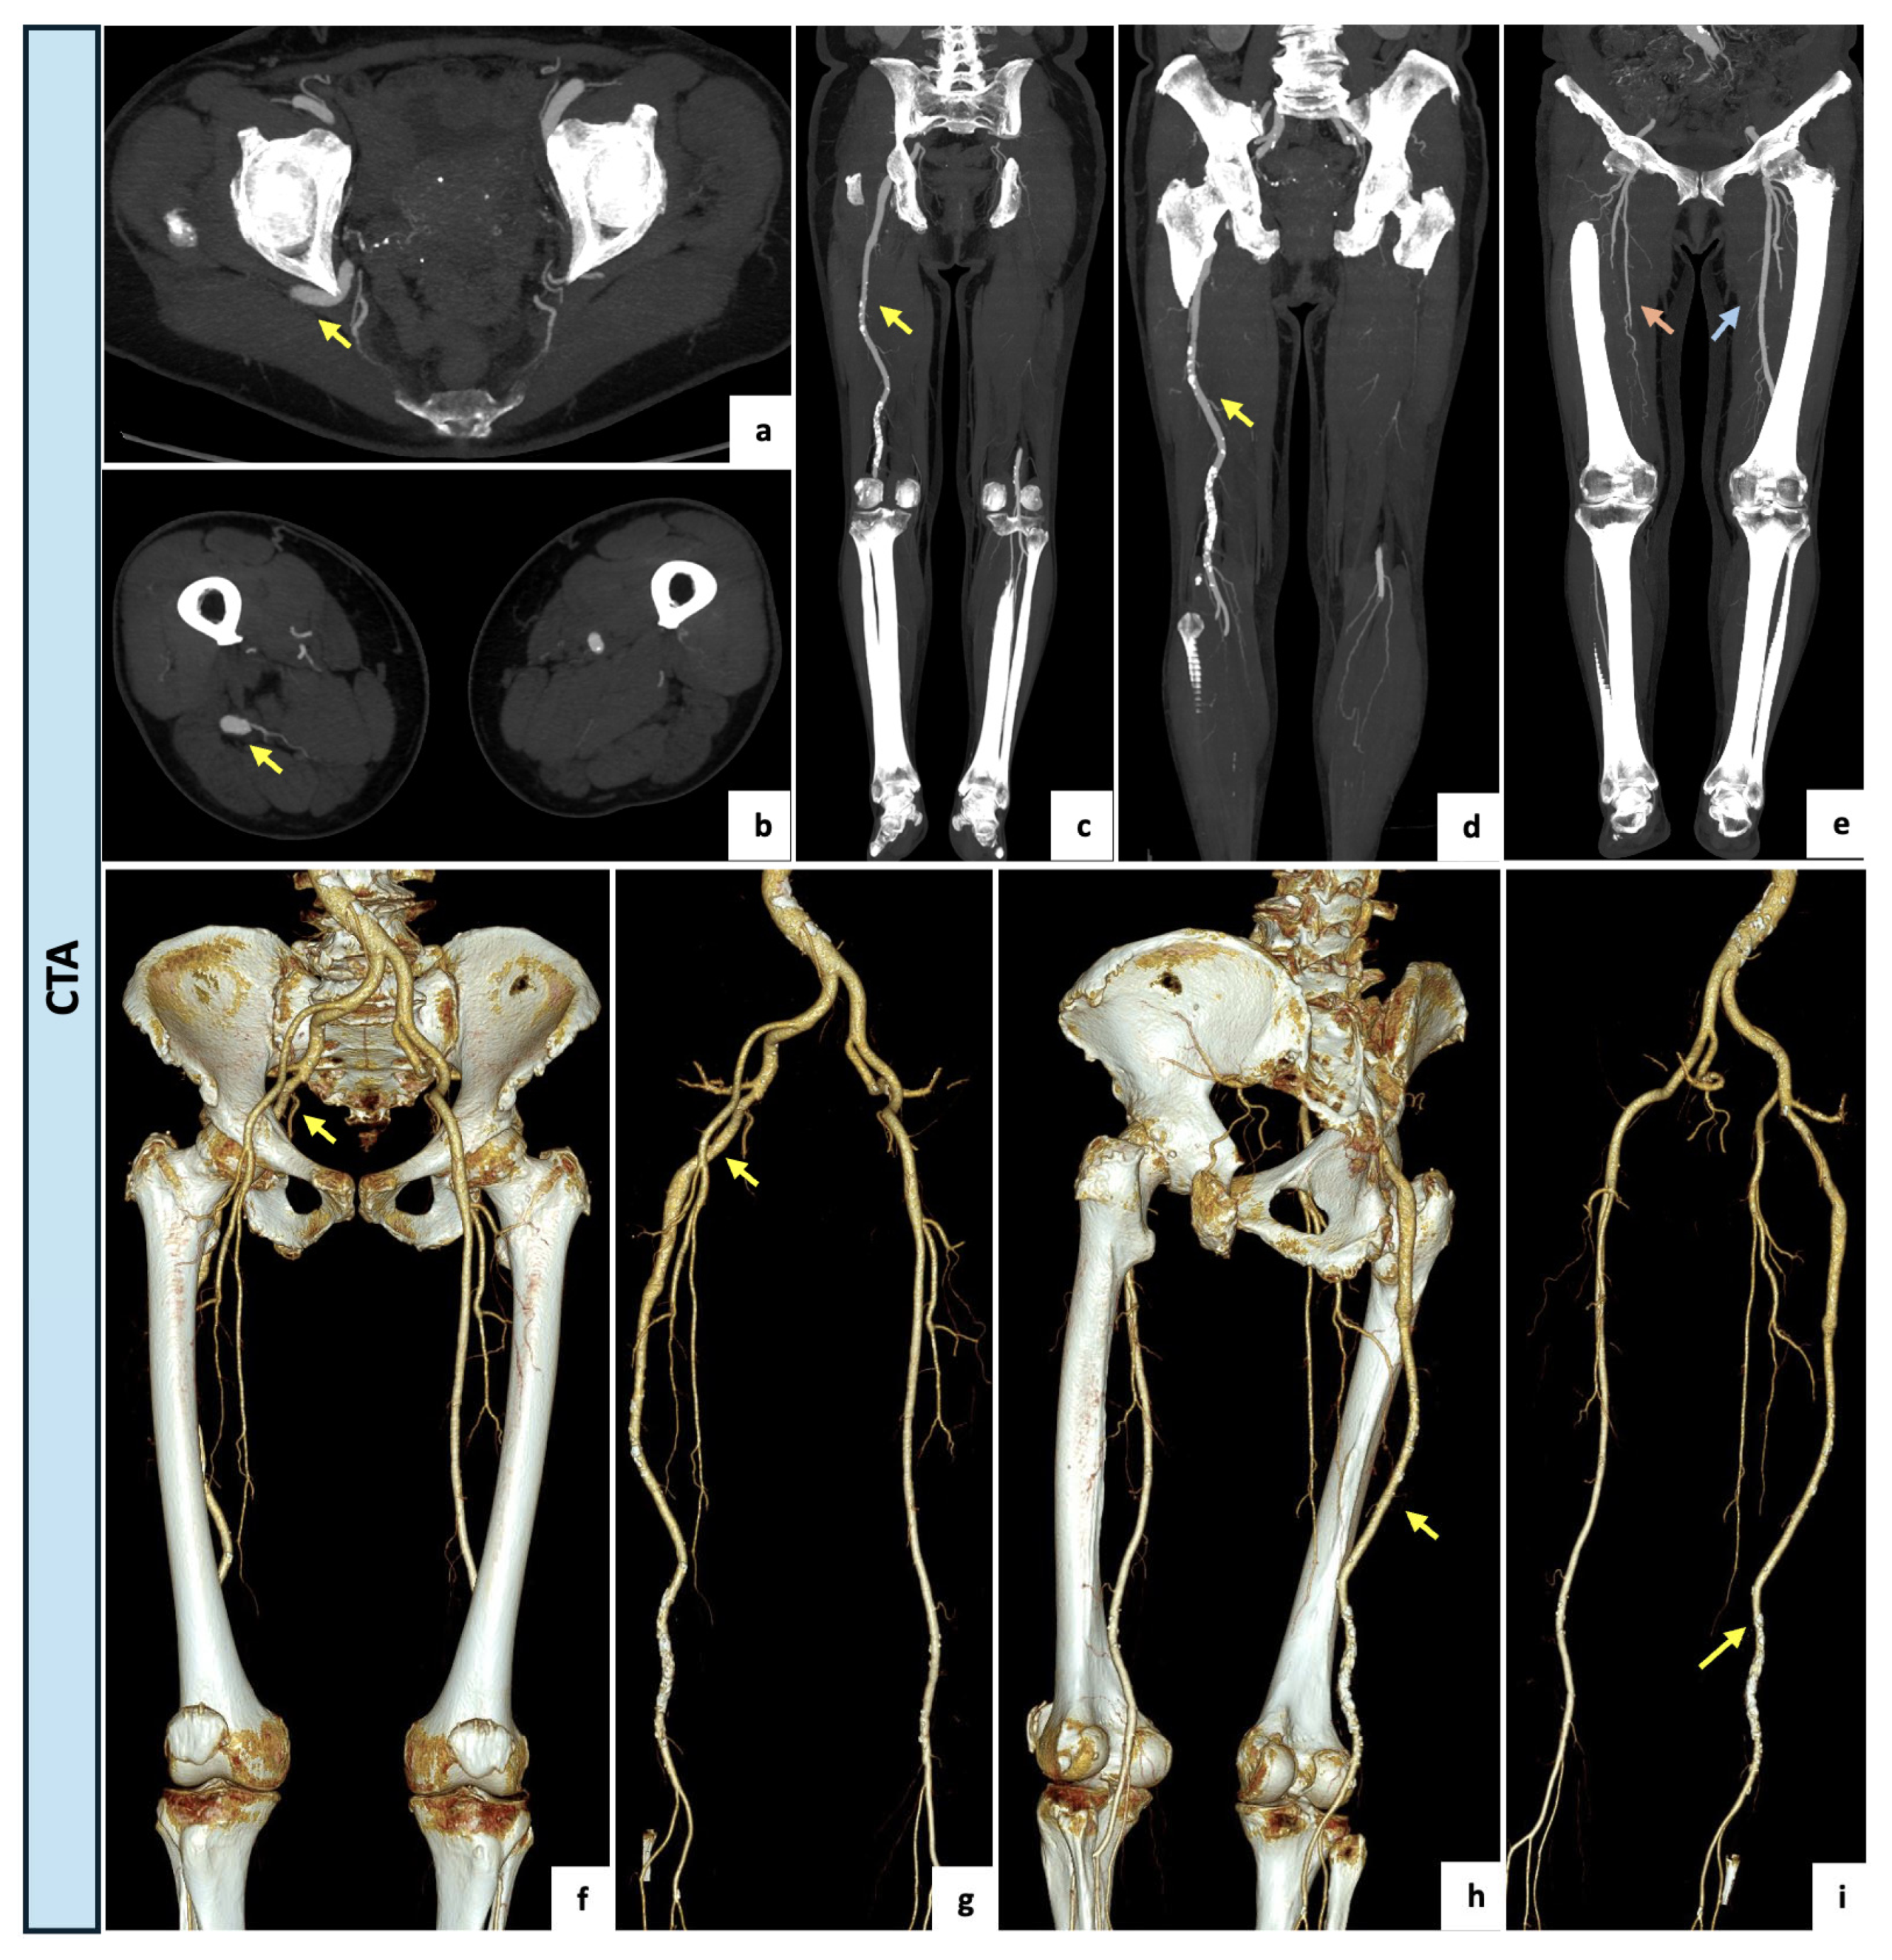

2.3. Case 3

An 81-year-old female with no major comorbidities and no history of peripheral vascular disease was referred to the Emergency Department of our hospital for the presence of moderate and recurrent back pain occasionally requiring pain medication. Upon examination, the patient exhibited an antalgic gait, normal vital signs, and regular perfusion, sensation and motor function of the lower extremities. A diminished right femoral pulse in combination with a regularly palpable popliteal pulse (named Cowie’s sign) was detected. The CTA examination (Figure 4) revealed the incidental finding of a right complete PSA originating from the internal iliac artery, with an incomplete ipsilateral SFA (type 2a). In this case, the PSA had developed as an ectatic arterial continuation (13 mm) of the internal iliac axis running through the greater sciatic notch, penetrating the bundles of the gluteus maximus muscle and following the proximal course of the sciatic nerve. Distally, the PSA had a regular course as popliteal–tibial axis with the high-origin anterior tibial artery. The SFA was proximally patent but diminutive and interrupted at Hunter’s canal. Due to the absence of aneurysmal degeneration and ischemic symptoms, the case was conservatively managed with a single anti-platelet agent, timed analgesics and instructions to avoid prolonged seated positions.

Figure 4.

(a–d) Axial and coronal maximal intensity projection views of the CTA demonstrating a right complete and ectatic PSA of 13 mm (yellow arrow) originating from the internal iliac artery and accompanied by an incomplete ipsilateral SFA interrupted at Hunter’s canal (type 2a). (e) Coronal view of lower limbs with a right incomplete ipsilateral SFA (orange arrow) and a regular contralateral femoral axis (blue arrow) (f–i) Three-dimensional reconstructions showing the ectatic PSA (yellow arrow) running through the greater sciatic notch, following the proximal course of the sciatic nerve and continuing as popliteal–tibial axis.